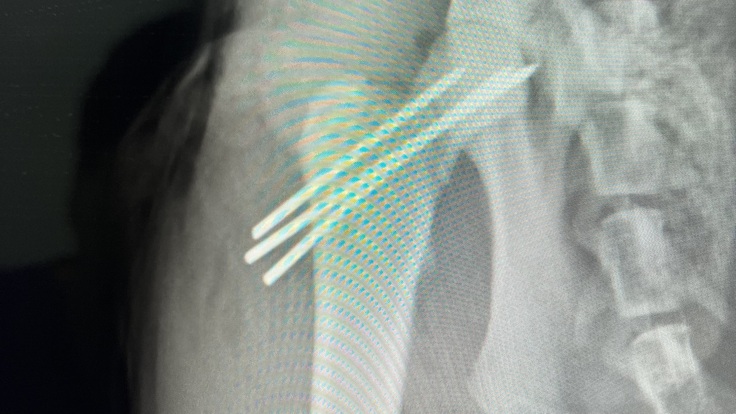

ちーちゃんの大腿骨頭骨折の手術が2/20無事に完了されました。

現在、骨と骨に3本のピンをさして留めている状況です。

お迎え当日、術後のレントゲン写真です

ピンを3本させましたと無事成功を伝えられました